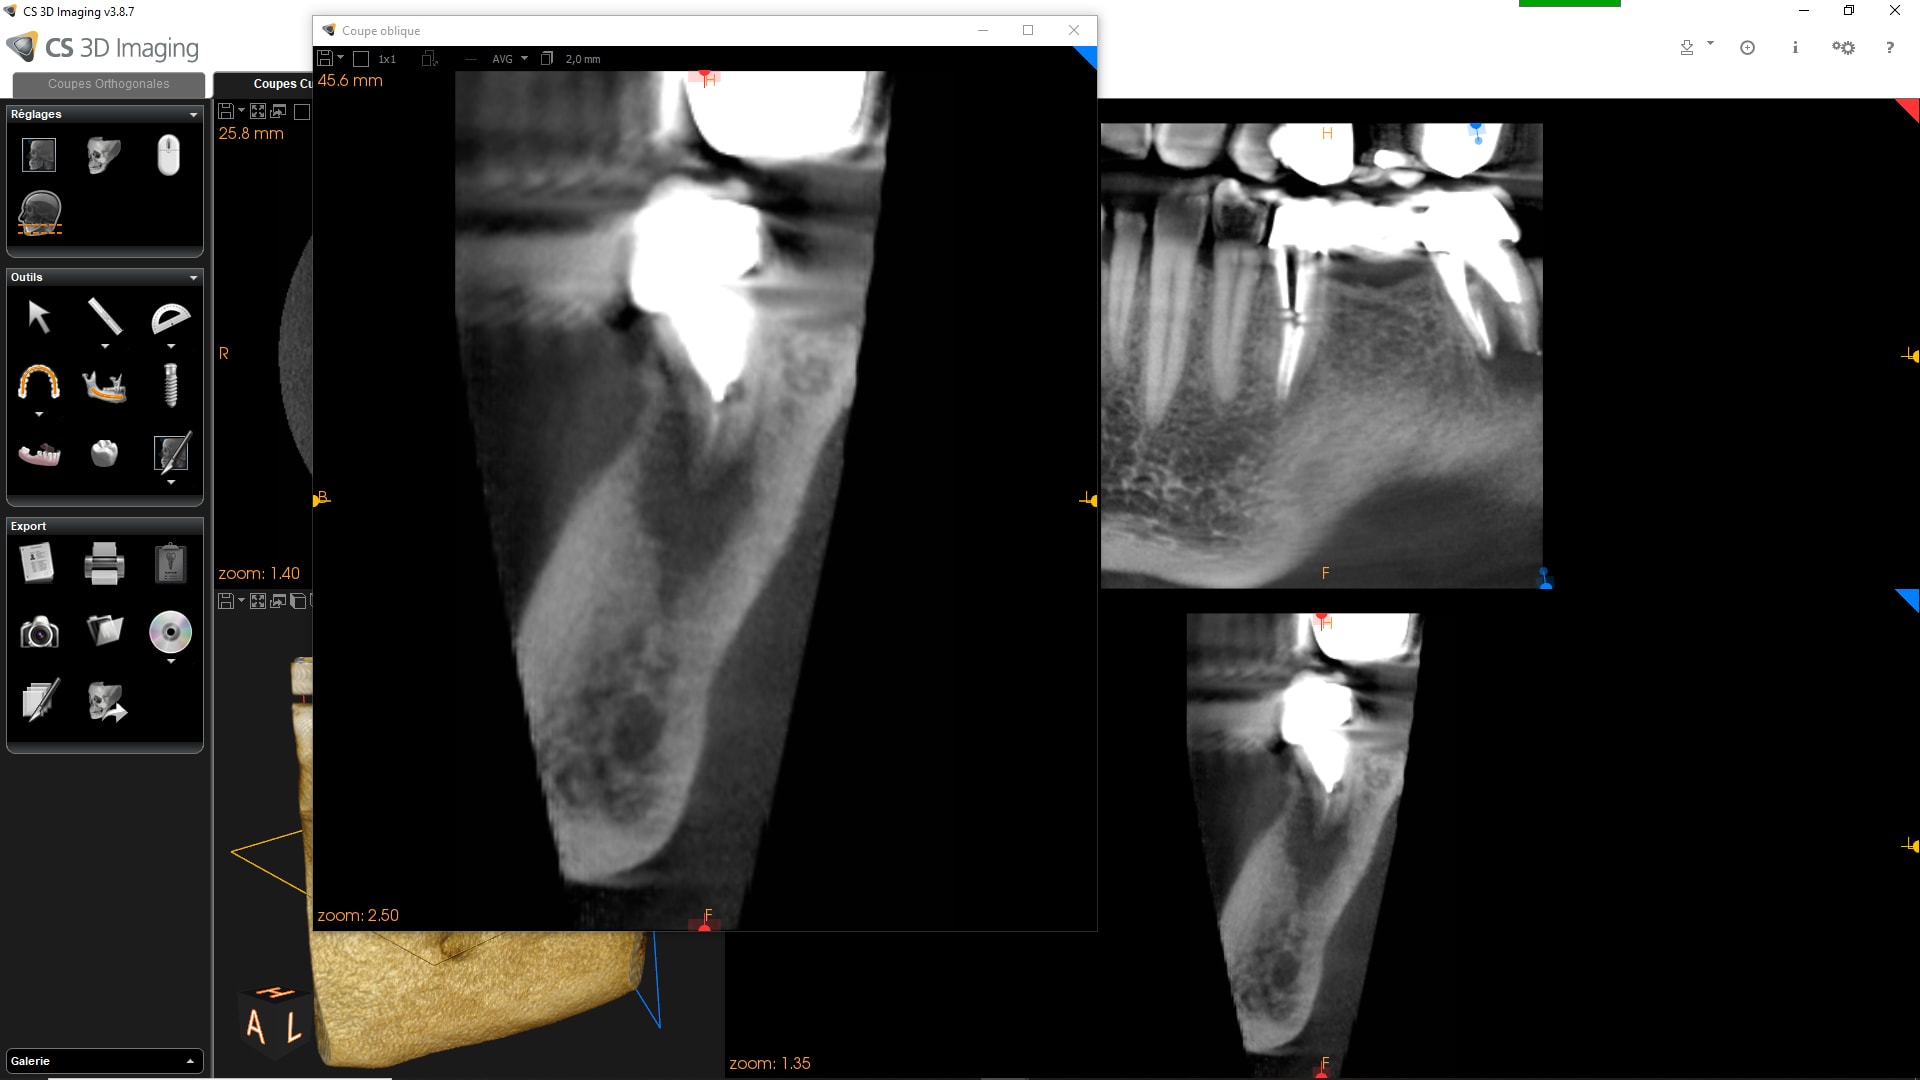

Effectivement première fois que cela m'arrive en 35 ans d'exercice !!

Traitement canalaire de la 47: la pâte à canaux ( Sealite Ultra ) a fusé au dela de l'apex lors de l'obturation à la guttachaude. Malheureusement le canal dentaire passe juste au niveau de l'apex et la pâte est rentré à l'intérieur.

La patiente n'a eu aucun signe pendant 3 jours puis paresthésie au niveau mentonnier ( pas au niveau labial) . La patiente décrit cela comme une fin d'anesthésie.

Quelles sont vos avis sur la récupération de la sensibilité ?

Depuis 3 semaines la paresthésie n'a pas changé ( diminué ou augmenté) .

Désolé pour les images cone beam: je n'arrive pas à les mettre dans le bon sens!!